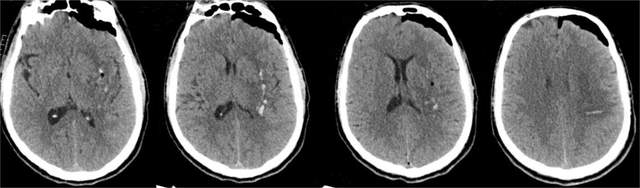

术前头颅CT显示,患者左侧基底核区脑出血

术后2小时头颅CT显示,血肿已清除

首例在澧县人民医院接受神经内镜下脑内血肿清除手术治疗的患者为一名50岁男性,有长期高血压病史,因“突发意识障碍伴右侧肢体偏瘫1小时”入院救治,检查确诊为左侧基底核区脑出血。在常德一医神经外科谢小明医生的指导下,澧县人民医院神经外科手术团队为患者实施了手术。手术顺利,术后复查颅脑CT血肿清除彻底,术后第1天患者神志即转清,经积极治疗后目前处于康复治疗中。